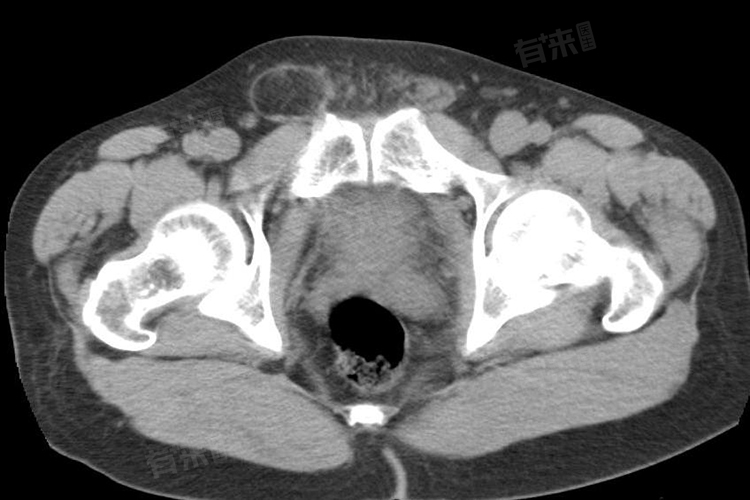

3、补片移位:疝气手术中的补片可能发生移位,需就医进行检查,若移位不严重可尝试手法复位并重新固定补片,若移位严重则需再次手术重新放置补片。

4、疝气复发:手术未能完全修复疝气导致复发,需重新评估病情,轻度复发可尝试保守治疗,如使用疝气带。严重的需再次手术修复,手术中要仔细检查疝环等部位确保修复牢固。